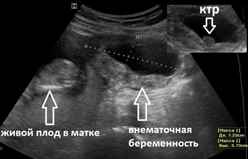

Видны ли признаки внематочной беременности на УЗИ?

УЗИ не всегда является информативным методом, так как на ранних сроках заметить плодное яйцо бывает невозможно и часто могут спутать сгустки крови или слизи в матке с маточной беременностью. Случалось наблюдать, что у женщины одновременно развивается две беременности, одна из которых маточная, которую и видит аппарат УЗИ, другая – внематочная. Если все же УЗИ тоже не подтверждает внематочную беременность, а подозрения на нее есть, то женщину могут положить в больницу для проведения соответствующей диагностики и лечения.